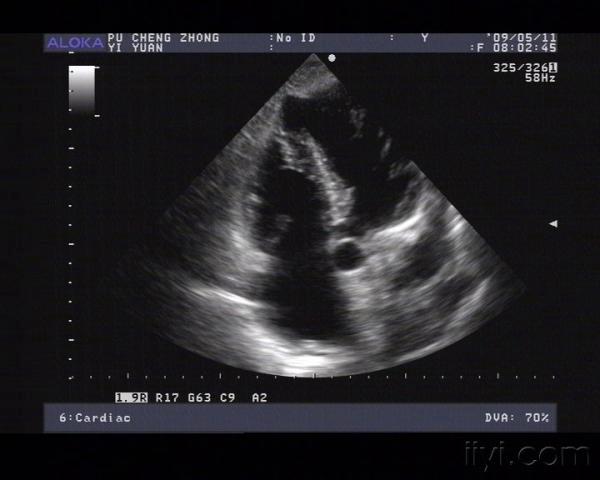

室壁瘤彩超图片,室壁瘤超声图片

室壁瘤破裂,经典!

心梗后室壁瘤还有假如何识别和诊断

一般情况尚可,但发现心脏确实发生重构,左室扩大,心尖形成室壁瘤

心梗后室壁瘤形成并室间隔穿孔

围手术期间,患者病情加重,复查心脏彩超示:ef40%,并可见左室后侧壁

室壁瘤超声图片

心脏室壁瘤超声图片

室壁瘤超声

室壁瘤

心室壁瘤

心尖室壁瘤